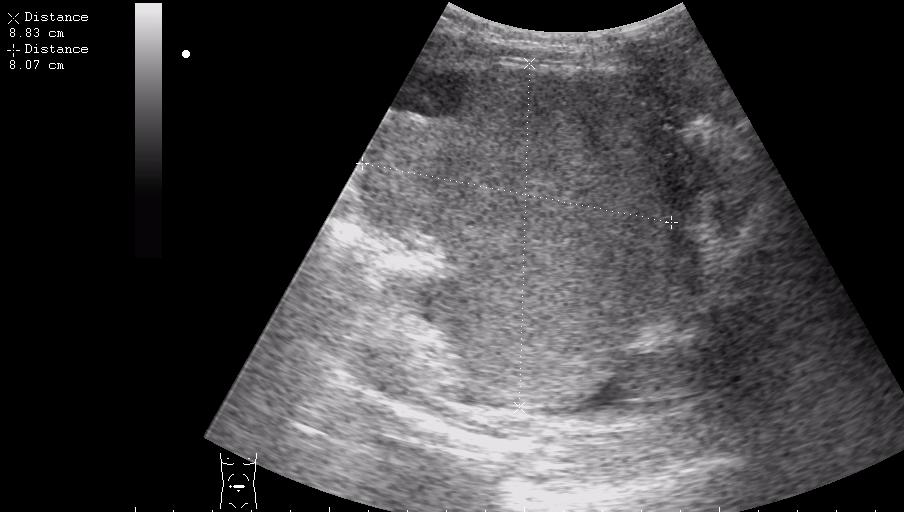

девочка 5 лет, опухоль правого яичника

опухоль правого яичника удалена 3 года назад

Если Это на стороне бывшей операции,то я за рецидив с МТ.Спасибо за бодимаркеры!

получается и в малом тазу и в брюшной полости

выпот похож на геморальгический (???)

первый: малый таз на боку видимо рецидив местный

если то что в брюшной полости не продолжение образования из малого таза....то как вариант mts в брюшине кишечника, в большом сальнике, забр л/у